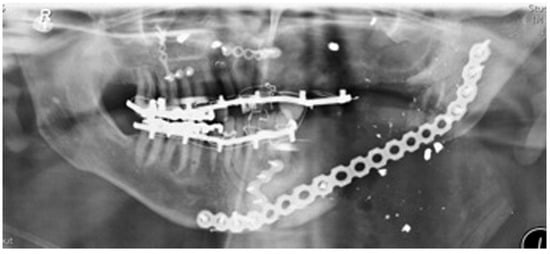

Staged reconstruction was defined as when the reconstruction with the free bone graft was performed as a secondary procedure. This secondary procedure was only performed when the oral mucosa had healed intraorally, sealing the mouth from the defect and the neck. A loadbearing locking mandibular plate was used to maintain the three-dimensional position of the bone and thus the occlusion (see Figure 1, Figure 2, Figure 3, Figure 4, Figure 5, Figure 6, Figure 7, Figure 8, Figure 9, Figure 10 and Figure 11).

Stage 1 surgery. Orthopantomography (OPT) to show locking plate to maintain the position of bony fragments whilst oral mucosa is healing in gun shot wound case.

Figure 11.

Orthopantomography(OPT) showing free bone graft placed in segmental defect.